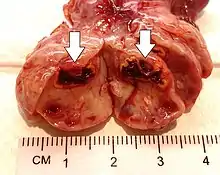

This type of functional cyst occurs after an egg has been released from a follicle. The follicle then becomes a secretory gland that is known as the corpus luteum. The ruptured follicle begins producing large quantities of estrogen and progesterone in preparation for conception. If a pregnancy doesn't occur, the corpus luteum usually breaks down and disappears. It may, however, fill with fluid or blood, causing the corpus luteum to expand into a cyst, and stay in the ovary. Usually, this cyst is on only one side, and does not produce any symptoms.[1][2]

A ruptured corpus luteum can cause hemoperitoneum with abdominal pain, and is a common condition in women of reproductive age. It may be confused with ectopic pregnancy.[4]